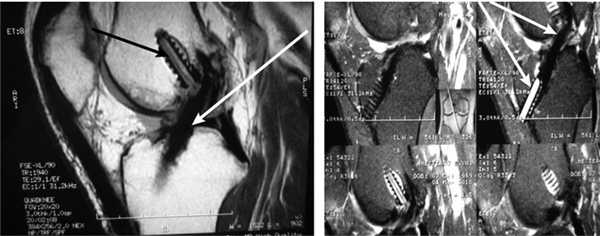

Все пациенты как с хронической патологией коленного сустава, так и с острой его травмой были обследованы с помощью МРТ-диагностики, что резко повысило качество дооперационной диагностики внутрисуставных повреждений коленного сустава. МРТ-диагностику выполняли на томографах 3—4-го поколения, с напряжением магнитного поля свыше 1,5 Tesla, разрешающая способность которых позволяла визуализировать повреждения связочных структур, менисков, суставного хряща, костной ткани коленного сустава (рис. 1 и 2).

Рис. 1. Острое повреждение ПКС коленного сустава. Стрелки указывают на зоны повреждения ПКС.

Рис. 2. МРТ старого повреждения ПКС коленного сустава. Стрелки указывают на зоны повреждения ПКС.